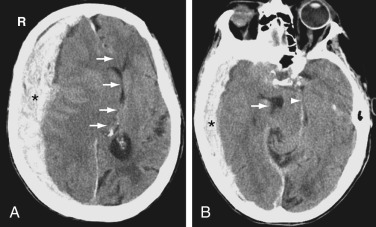

ICH